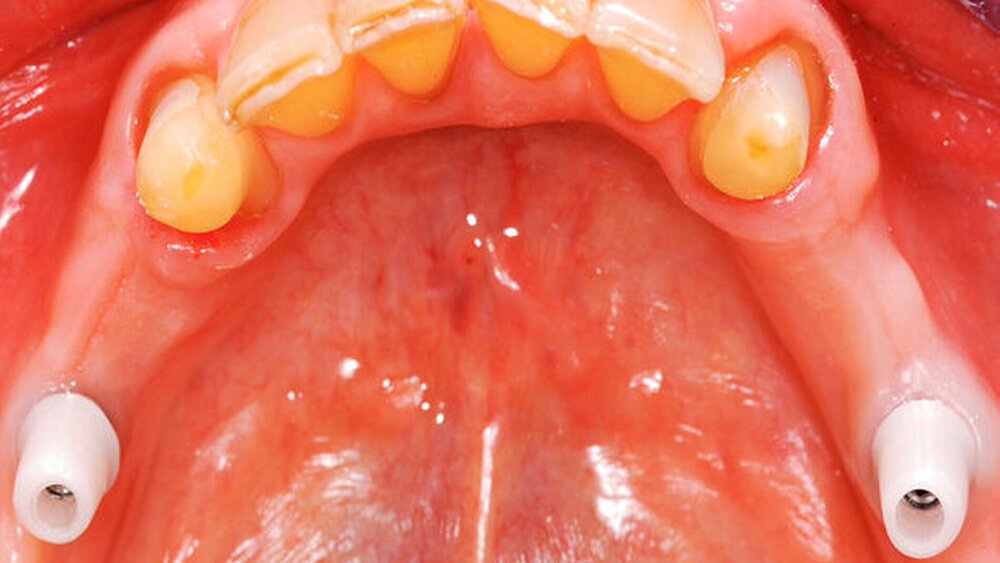

Bei der Rehabilitation von posterior verkürzten Zahnreihen zeigten Verbundbrücken aus verblendeten Zirkonoxidgerüsten nach drei Jahren eine Überlebenswahrscheinlichkeit von 93,9 Prozent (Abbildungen 1 bis 3). Im Rahmen von verschiedenen Studien wurden Überlebensraten für metallbasierte Verbundbrücken nach fünf Jahren zwischen 91,6 und 97,6 Prozent angegeben [Koth et al., 1988; Nickenig et al., 2006; Pieralli et al., 2018], nach zehn Jahren zwischen 81,7 [Mundt et al., 2012] und 87,8 Prozent [Nickenig et al., 2008]. In retrospektiven Untersuchungen, die explizit aus der Analyse der Daten für diese Leitlinie ausgeschlossen wurden, wird von Überlebensraten von bis zu 100 Prozent nach sechs Jahren berichtet [von Stein-Lausnitz et al., 2019].